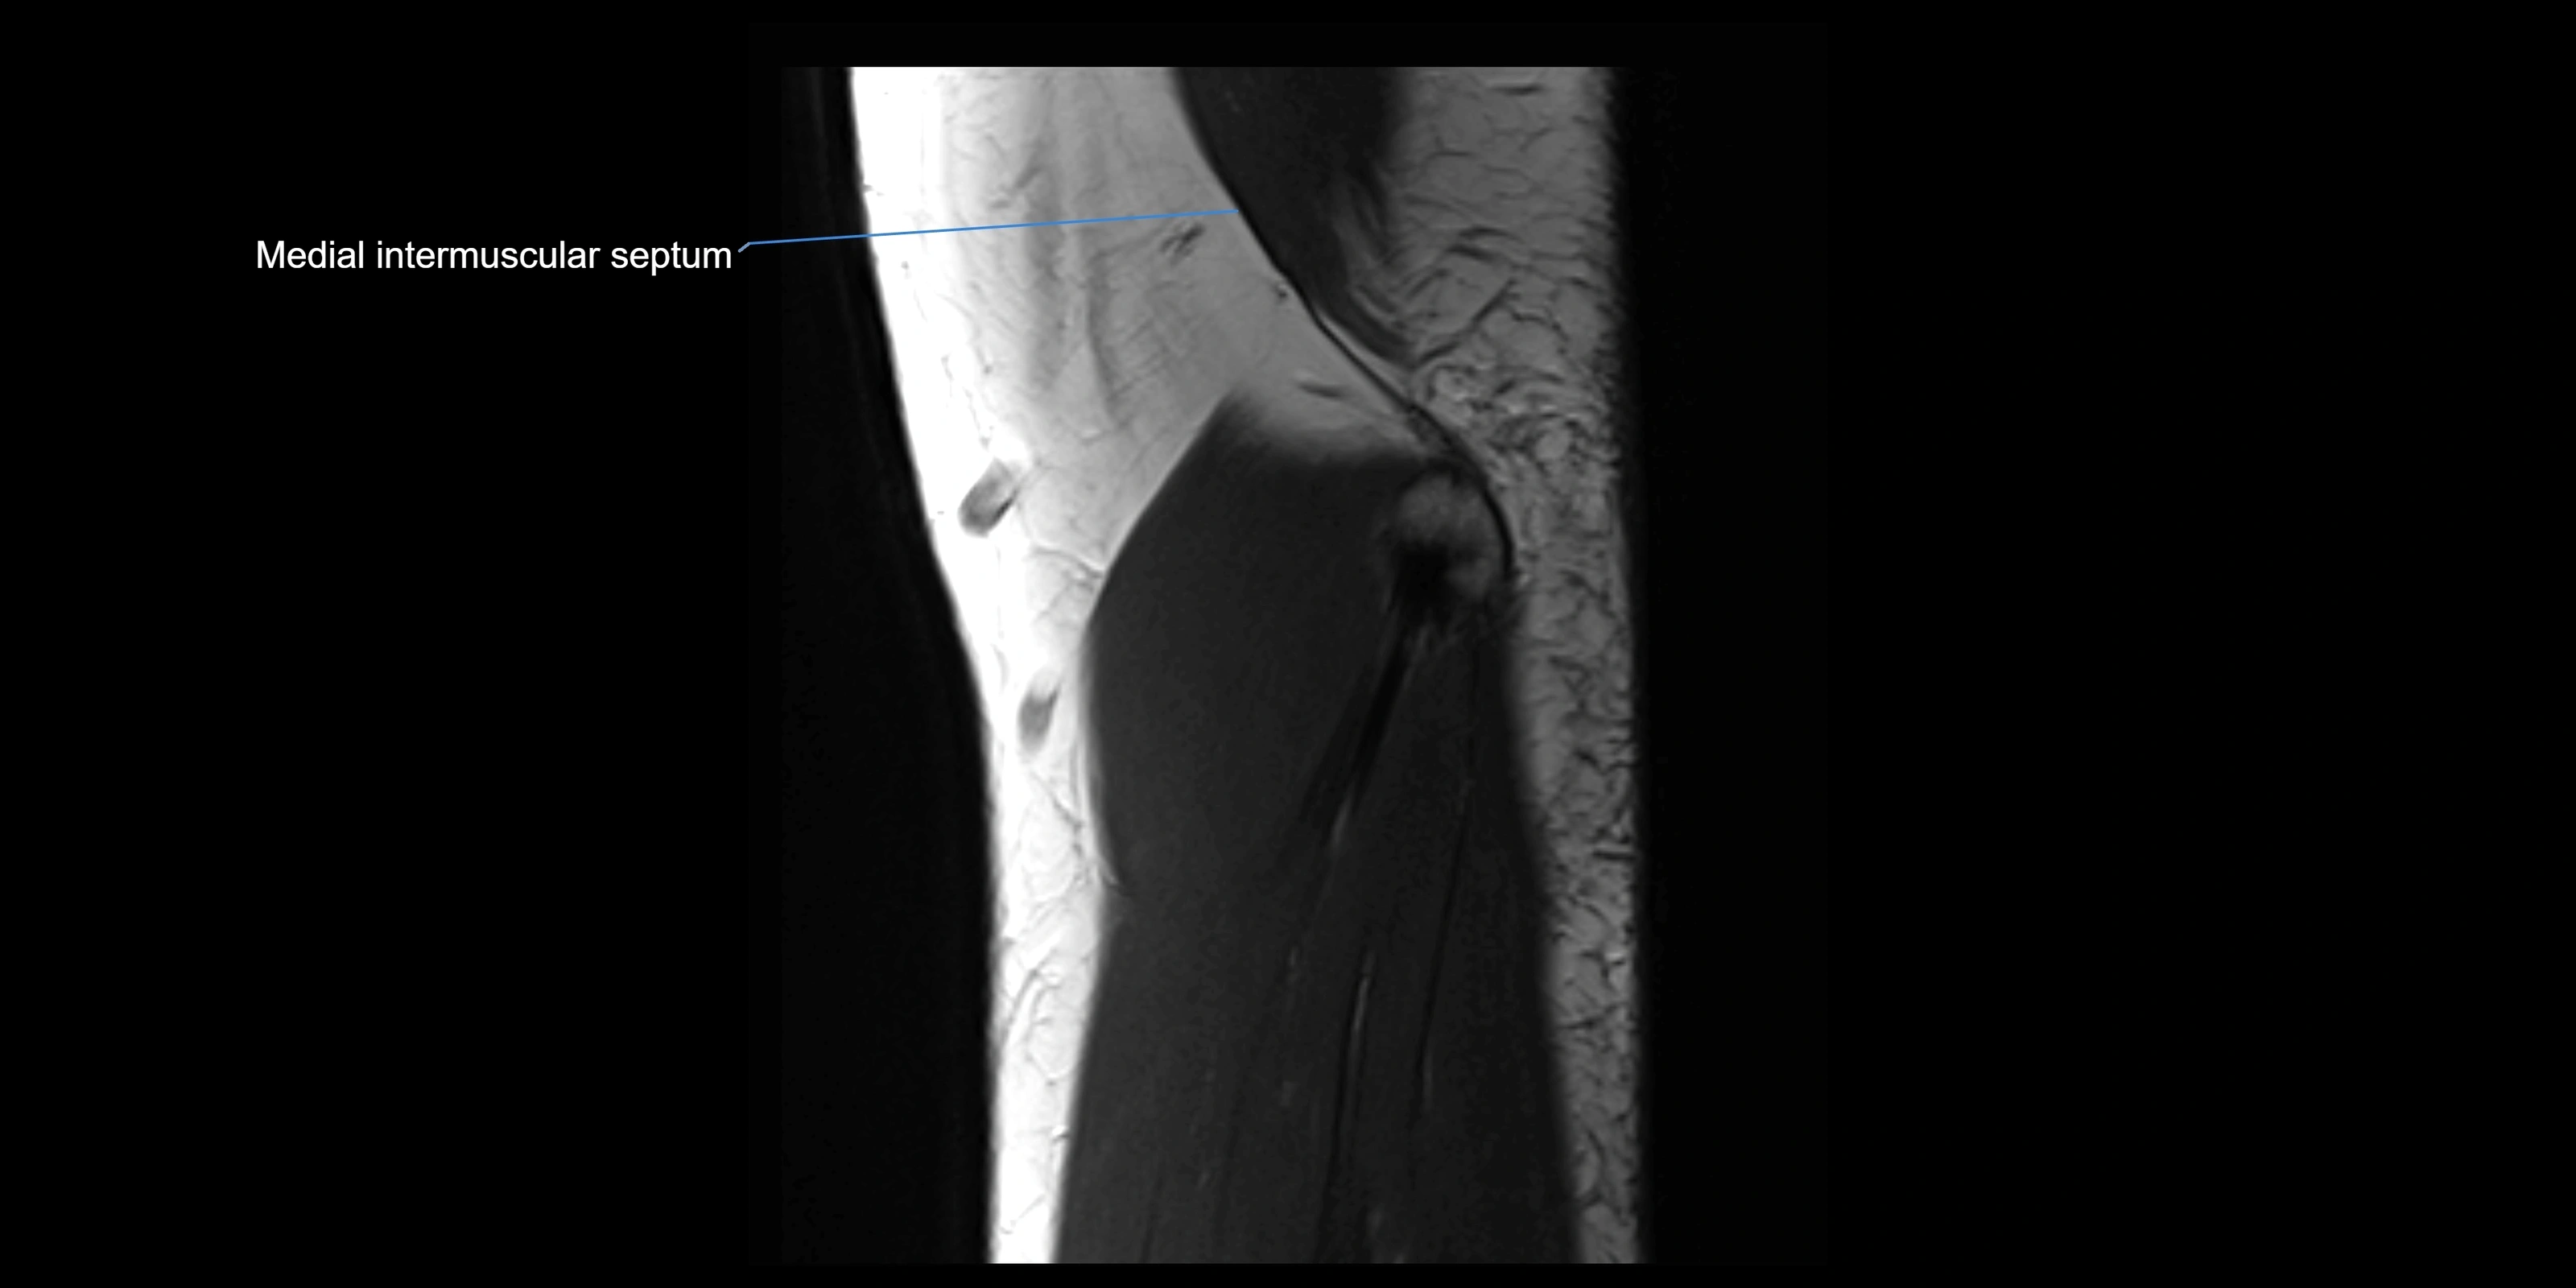

MRI images

image